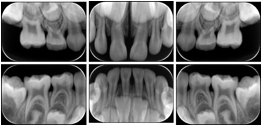

3. A dental provider wishes to capture a series of DICOM IO images for the patient’s dentition. The tooth morphology, teeth are divided into molars, premolars, canines and incisors, and a number of images for each jaw. The anatomic information was captured utilizing the triplet of schema. This standard code sequence is based on ISO 3950-2010, Dentistry - Designation system for teeth and areas of the oral cavity.

Every IO image should have anatomic information either through the primary or modifier sequence.

In most standard cases, images are oriented in structured layouts. These structured displays are useful to be shared between providers for reference purposes.

Table OO.1.1-1 shows structured display standard templates, where Viewset ID is based on the Japanese Society for Oral and Maxillofacial Radiology (JSOMR) classification provided by JIRA (Japan Medical Imaging and Radiological Systems Industries Association, www.jira-net.or.jp). Expected or typical teeth to be imaged location, region and designation codes are based on ISO 3950-2010, Dentistry - Designation system for teeth and areas of the oral cavity. For all the hanging protocols listed in OO.1.1-1, the value to use for Hanging Protocol Creator (0072,0008) is "JSOMR" and the value to use for Hanging Protocol Name (0072,0002) does not include "JSOMR" (e.g., "DL-S001A", not "JSOMR DL-S001A").